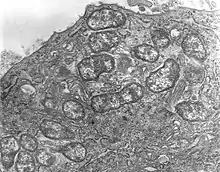

Orientia tsutsugamushi

Genus: Orientia

Species: Orientia tsutsugamushi